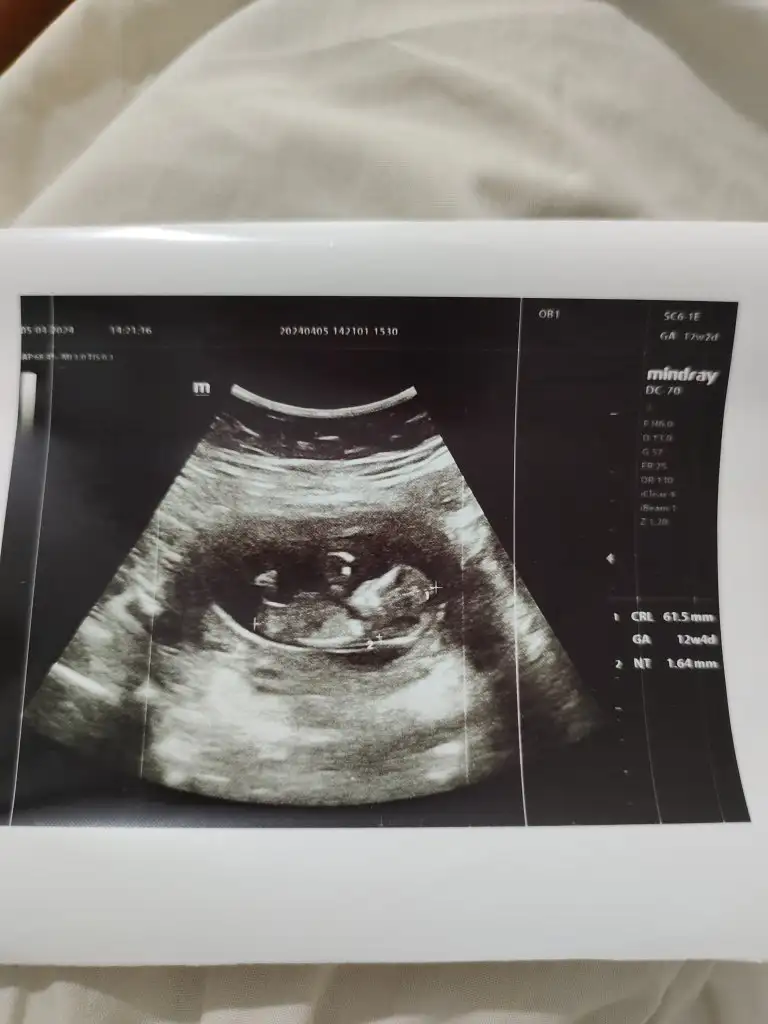

Kızlar çok şükür bebeğim iyi herşey yolunda cinsiyetini kıza benziyor bir ay sonra kesinleşir dedi sizce ne bakar mısınız 😇12+2 bugün

Eklentiler

• IMG_20240405_161406.webp

IMG_20240405_161406.webp

27 KB · Görüntüleme: 83

• IMG_20240405_161353.webp

IMG_20240405_161353.webp

28,1 KB · Görüntüleme: 88